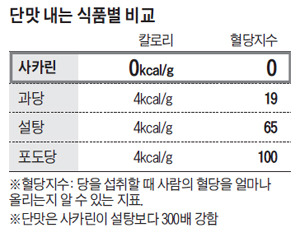

사카린은 1879년에 처음 발견된 인공 감미료로, 설탕보다 훨씬 더 달콤한 맛을 가지고 있어요. 이 때문에 다양한 식품에 사용되며, 특히 다이어트 음료나 저칼로리 간식에서 많이 찾아볼 수 있어요. 사카린은 혈당 지수가 0으로, 당뇨병 환자에게 안전한 대체 감미료로 알려져 있어요.

6. 사카린과 다른 감미료 비교

사카린은 다른 감미료와 비교했을 때 칼로리가 0인 점이 큰 장점이에요. 예를 들어, 설탕은 4 kcal/g, 아스파탐은 4 kcal/g인데 반해, 사카린은 0 kcal/g로 혈당에 영향을 미치지 않아요. 이러한 특성 덕분에 다이어트나 당뇨 관리에 유용하게 사용될 수 있어요.